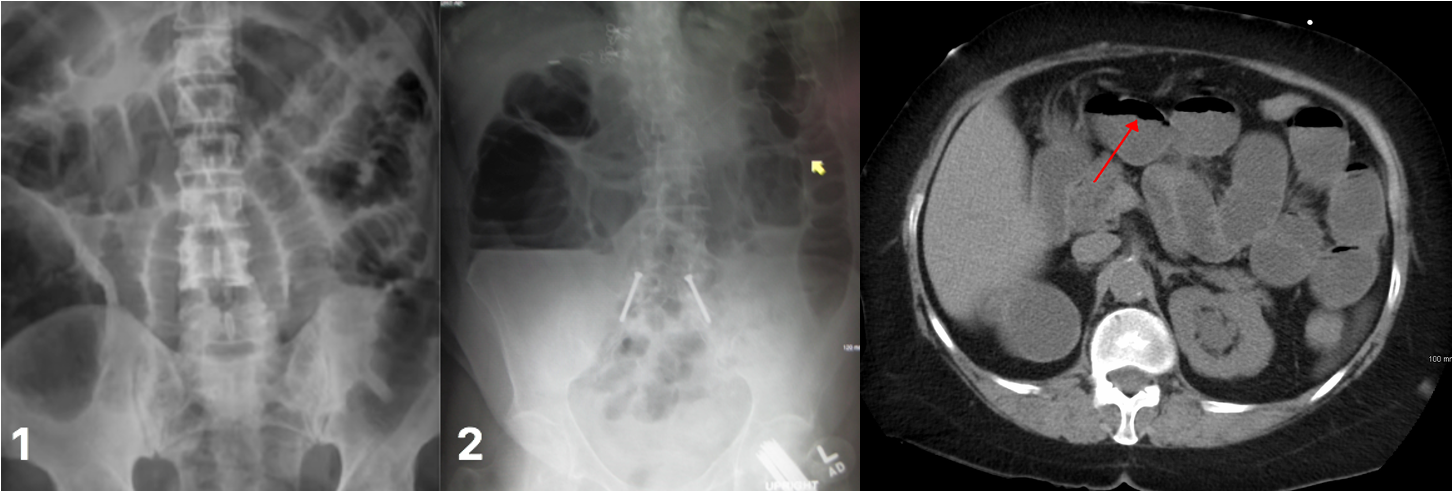

Radiological appearances:

Dilatation of bowel loops proximal to the obstruction: 3-6-9 rule :To help guide the identification of bowel dilatation on imaging. Transverse diameter greater than the following indicates dilation: Small bowel > 3 cm Large bowel > 6 cm Cecum > 9 cm

- SBO: Dilated loops are predominantly central.

- LBOÂ : Dilated loops are predominantly peripheral.

CT abdomen with contrast (Triple)